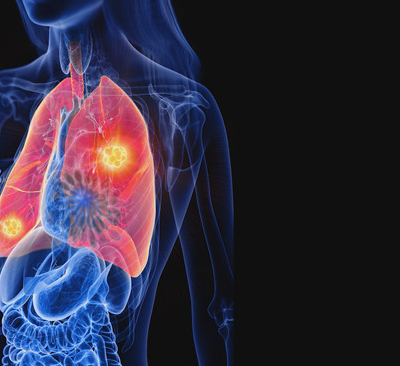

오늘은 단순한 감기와는 달리, 폐에 염증이 생기는 심각한 질환인 폐렴의 증상에 대해 이야기하려 합니다. 폐렴은 세균, 바이러스, 곰팡이 등 다양한 원인에 의해 발생하며, 특히 면역력이 약한 어린이나 노인에게 치명적일 수 있습니다.

폐렴은 보통 갑작스럽게 시작되며, 호흡기 증상과 함께 전신 증상이 복합적으로 나타납니다. 다음은 폐렴 환자들이 흔히 겪는 10가지 주요 증상입니다.